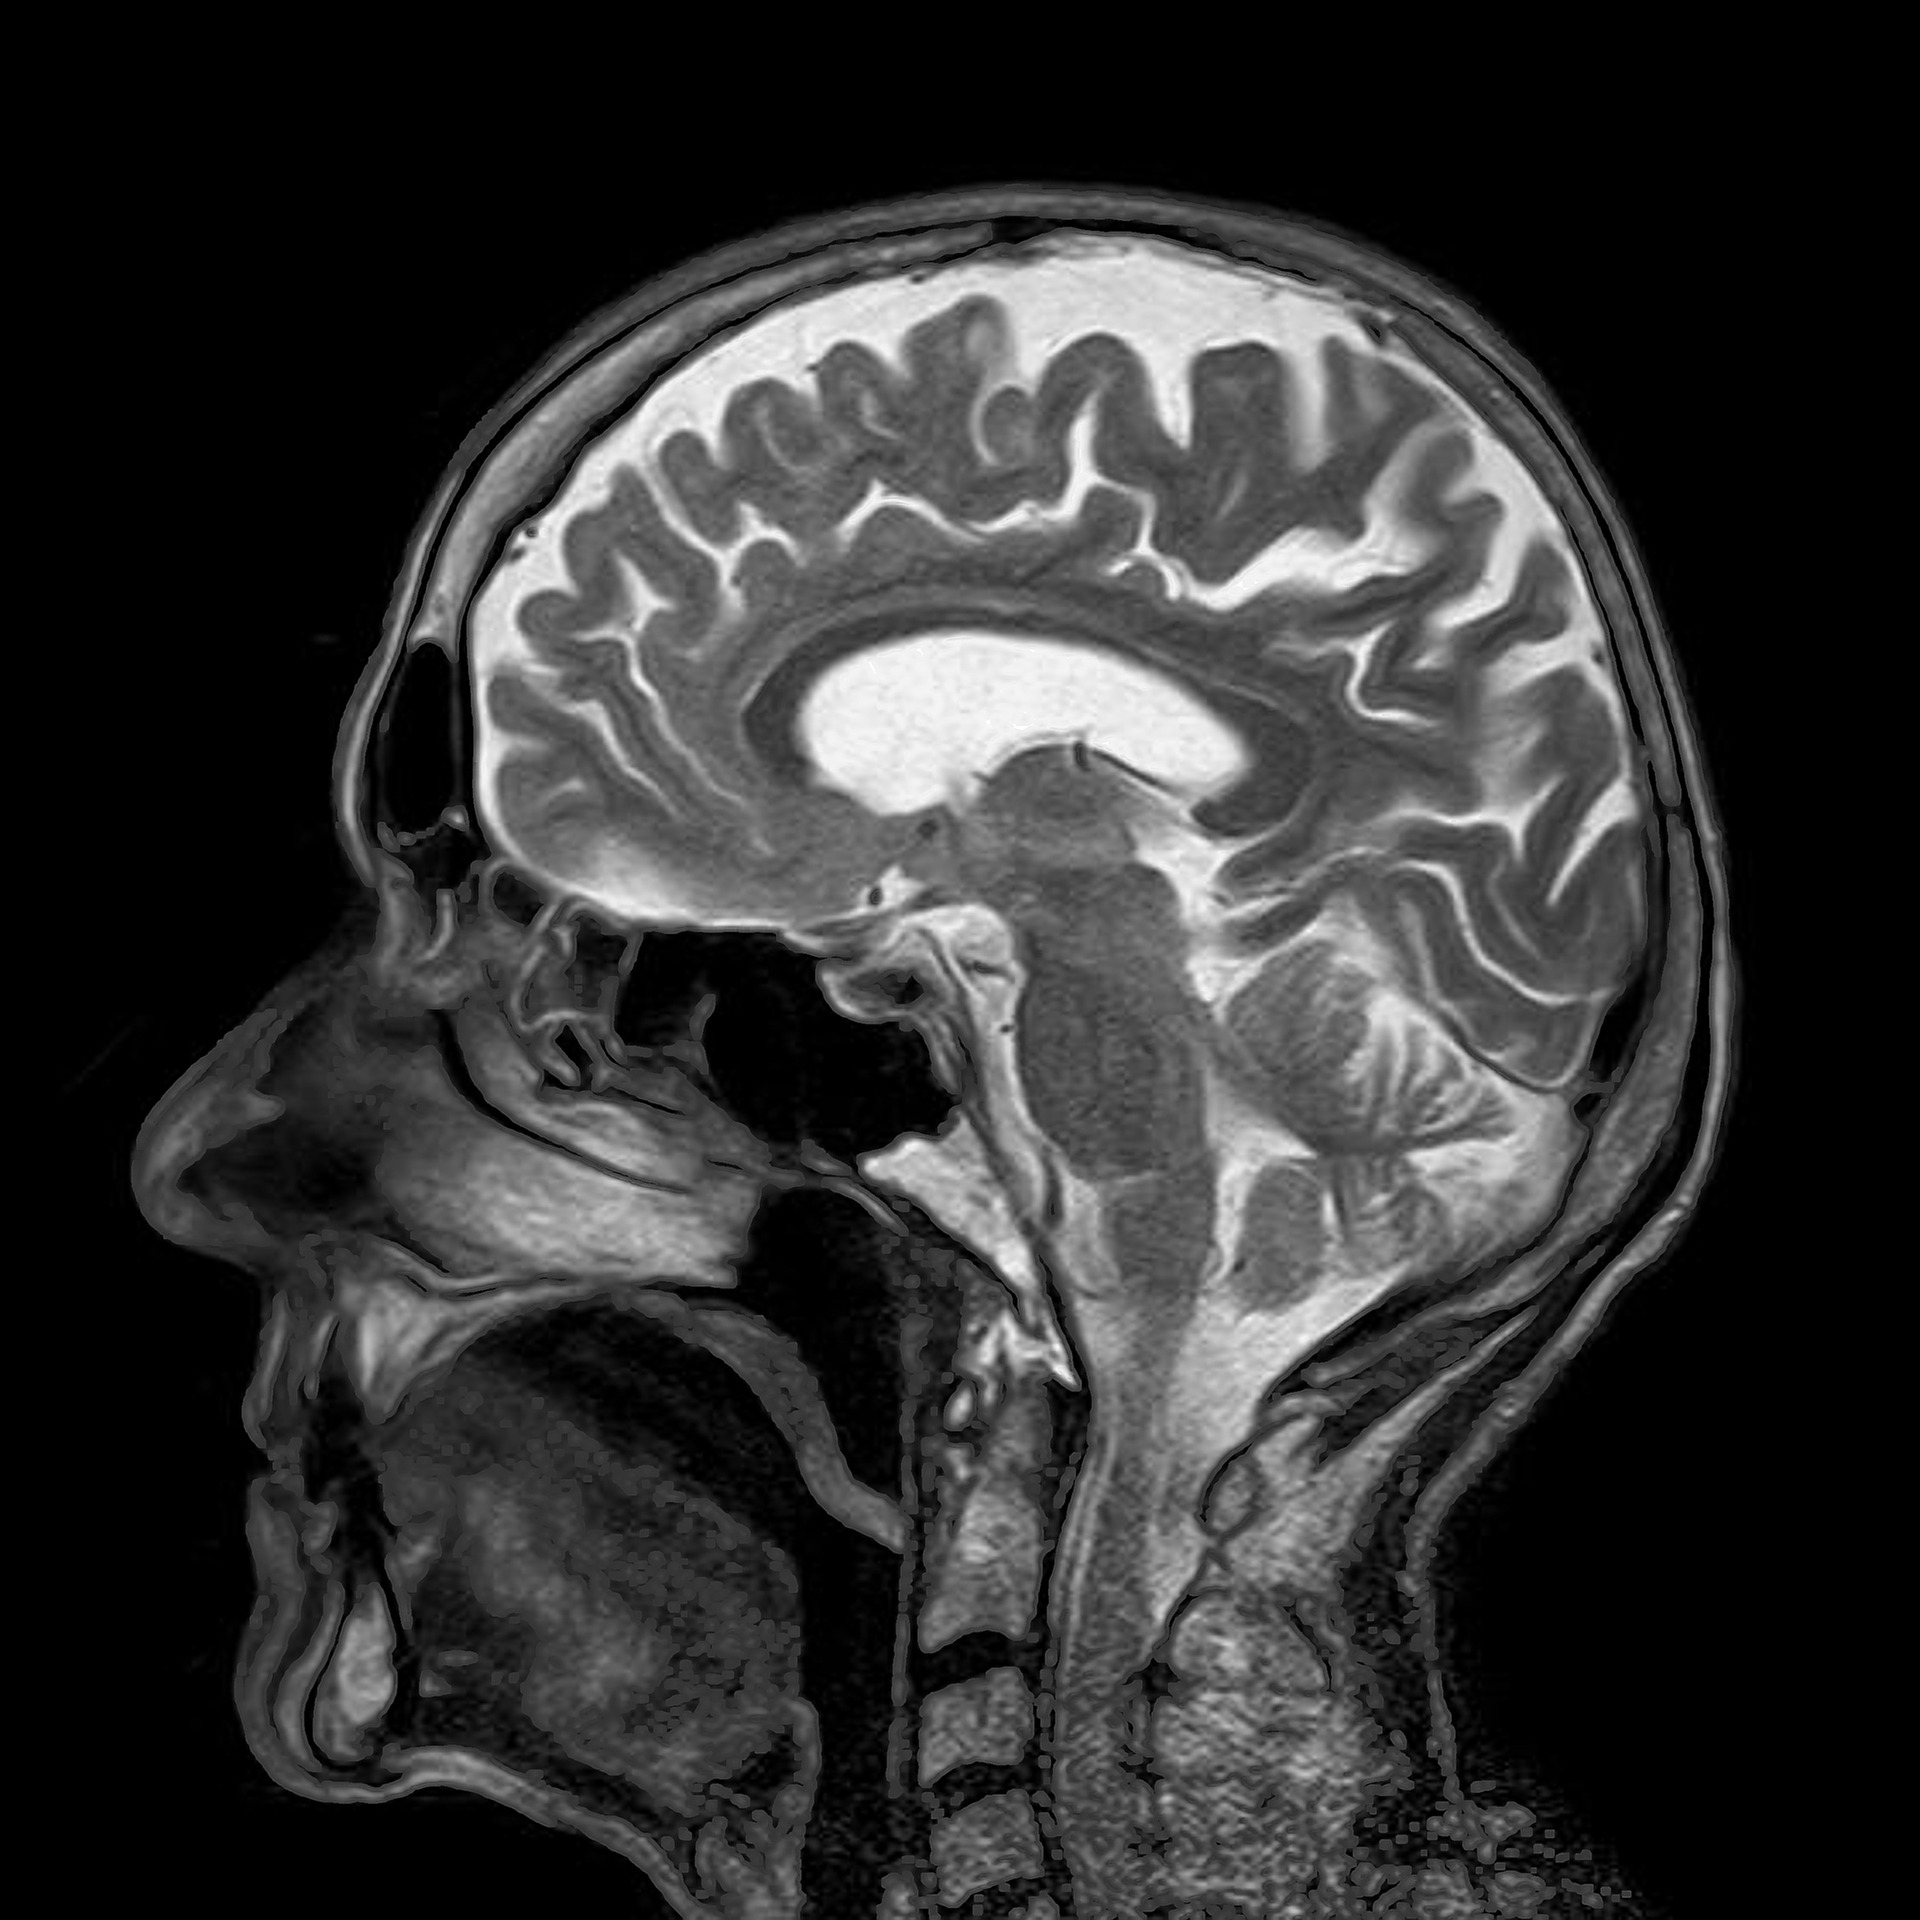

Важно понимать, что речь идет не о магическом исцелении, а о высокоточной медицинской процедуре под контролем МРТ. Используемое оборудование, такое как системы Exablate Neuro от компании Insightec, уже одобрено FDA для лечения болезни Паркинсона и эссенциального тремора. Теперь этот же инструментарий адаптируют для психиатрии и наркологии. В отличие от таблеток, которые действуют на весь организм и часто имеют побочные эффекты, ультразвук бьет с точностью до миллиметра, не затрагивая соседние участки мозга, отвечающие за память или эмоции.